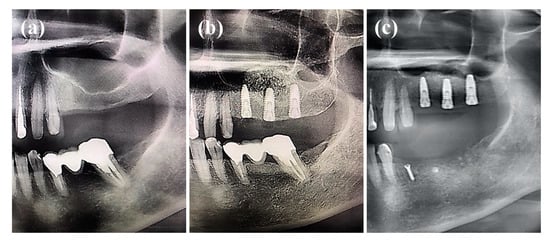

Figure 6 shows a panoramic image of the patient before and after obtaining a bone graft. A vertical bone loss in the posterior maxillary region (Figure 6a) caused the sinus lifting, and an additional bone graft was required to obtain adequate bone volume before implant placement [,,]. The panoramic image immediately after sinus lifting and the implant of a bone graft material (Figure 6b) indicate that the bone graft material fills the space after sinus lifting. At the six months of follow-up after treatment, the bones in the implanted area were more radiopaque, and all of the bone graft material was absorbed.

Figure 6.

Panoramic images: (a) before treatment, (b) immediately after treatment, and (c) six months after treatment.

The cone-beam CT images before treatment also showed a vertical bone loss in the posterior maxillary region (Figure 7). In the jaw, the maxilla region is the most frequently experiencing vertical bone loss and the most difficult to treat [,]. Therefore, both moderate and severe bone loss in this region require a bone graft to treat it [].

Figure 7.

Cone-beam computed tomography (CT) images before treatment.